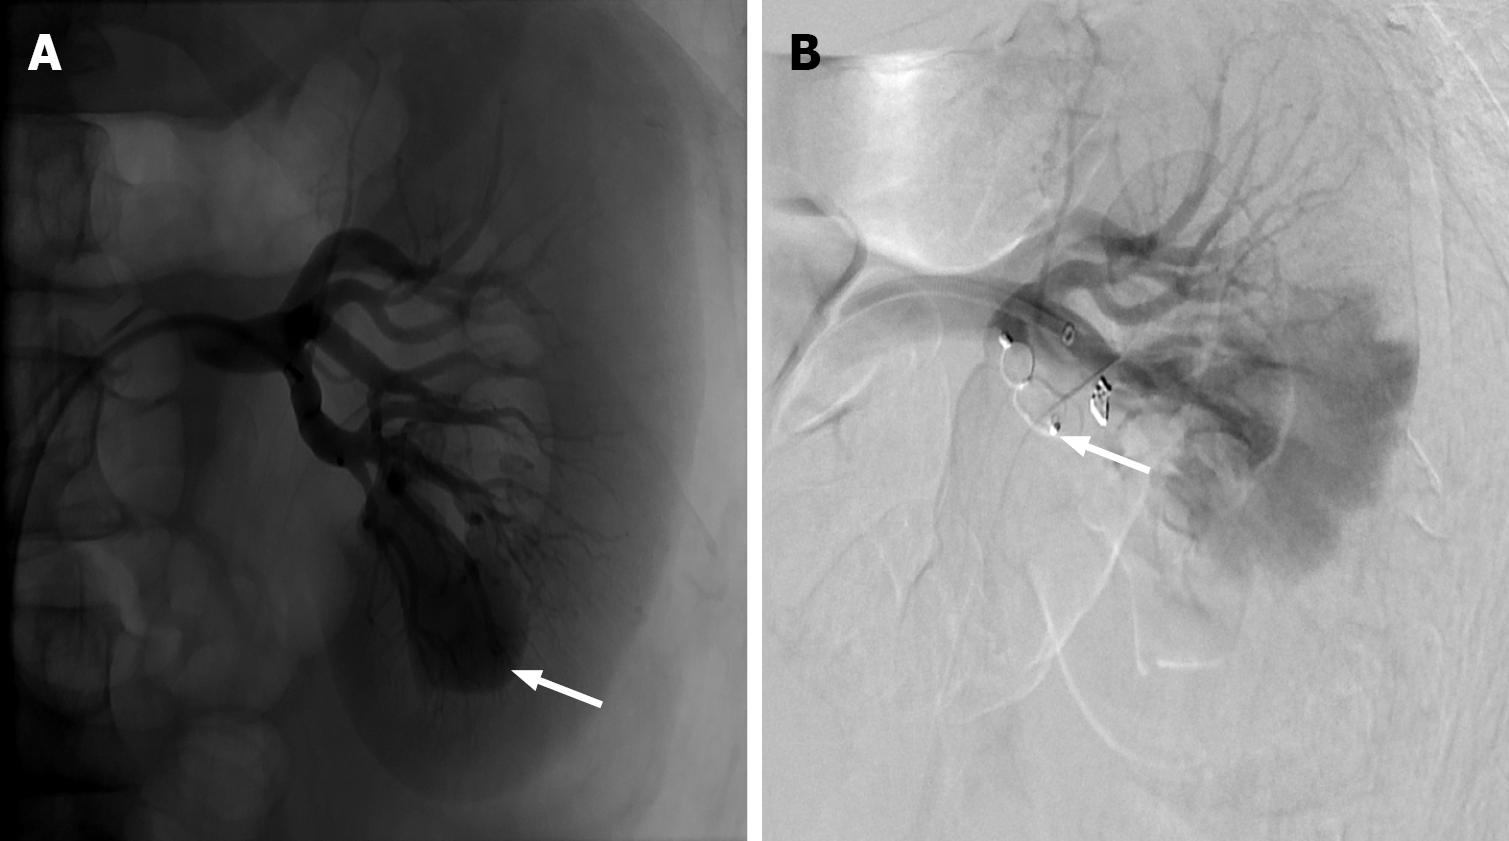

Figure 9 Renal arterio-venous fistula.

A: Left renal artery angiogram demonstrating a large inferior pole pseudoaneurysm (white arrow); B: Subsequent treatment with an Amplatzer plug (white arrow) and a single coil, with successful occlusion of the pseudoaneurysm. Additionally, early venous filling was noted during examination, concerning for traumatic renal arterio-venous fistula.